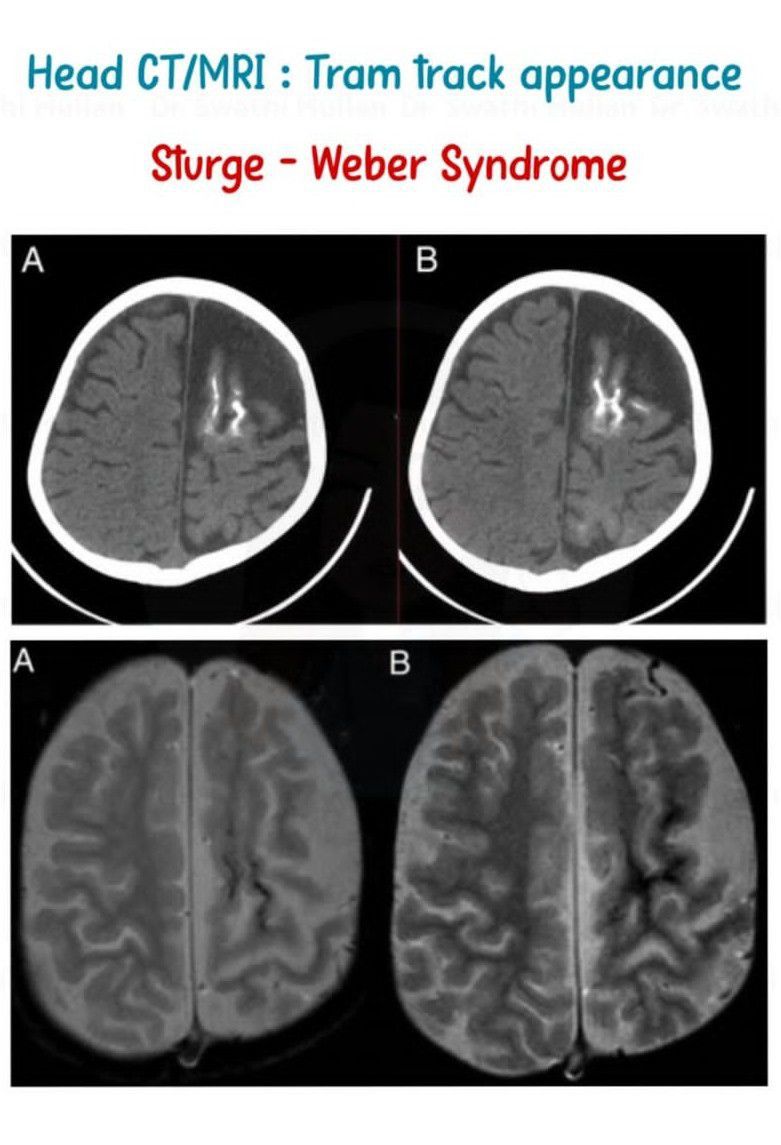

Tram Track Appearance III

Tram track appearances or tram track signs are medical signs that bear some resemblance to tramway tracks. They are seen in different conditions By: https://www.instagram.com/p/C6ifvK7B6ia/?utm_source=ig_web_copy_link